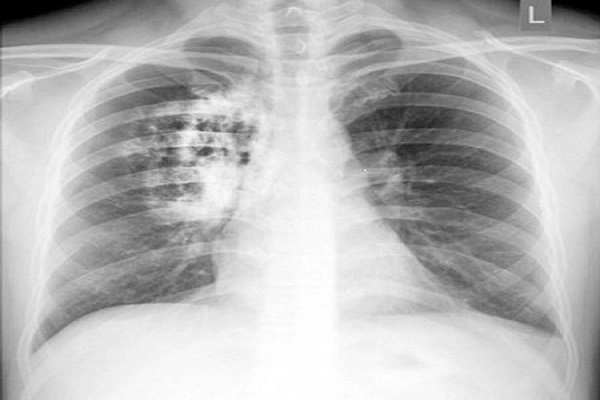

Bạn sẽ phải rùng mình khi chiêm ngưỡng hình ảnh bệnh lao phổi là như thế nào dưới ống kính y học thực tế. Những bức ảnh chụp X-quang cho thấy phổi bị tổn thương nặng, xuất hiện những đốm trắng mờ như bóng ma ám ảnh. Không chỉ là các tổn thương vật lý, đây còn là những “chứng tích sống” của căn bệnh âm thầm hủy hoại cơ thể qua từng hơi thở. Từ viêm nhẹ đến tổn thương lan rộng, hình ảnh bệnh lao phổi khiến người xem không thể rời mắt vì mức độ nghiêm trọng mà nó thể hiện rõ ràng qua từng chi tiết.

Cảnh báo: tổng hợp ảnh bệnh lao phổi chân thực này không dành cho người yếu tim. Đây là loạt hình ảnh y khoa được các chuyên gia sưu tầm và xác thực, ghi lại quá trình tiến triển của bệnh từ giai đoạn đầu đến giai đoạn nguy kịch. Từng mảng mô phổi bị ăn mòn, xơ hóa, hoại tử được phơi bày rõ nét dưới ánh sáng X-quang lạnh lùng. Những hình ảnh này không chỉ mang tính chất minh họa y học, mà còn là hồi chuông cảnh tỉnh cho bất kỳ ai còn lơ là với căn bệnh nguy hiểm này.

Thông qua những hình ảnh bệnh lao phổi thực tế, người đọc có thể hiểu rõ hơn về diễn biến của bệnh. Việc theo dõi hình ảnh giúp phát hiện sớm, điều trị đúng cách và ngăn ngừa biến chứng nghiêm trọng có thể xảy ra trong tương lai.